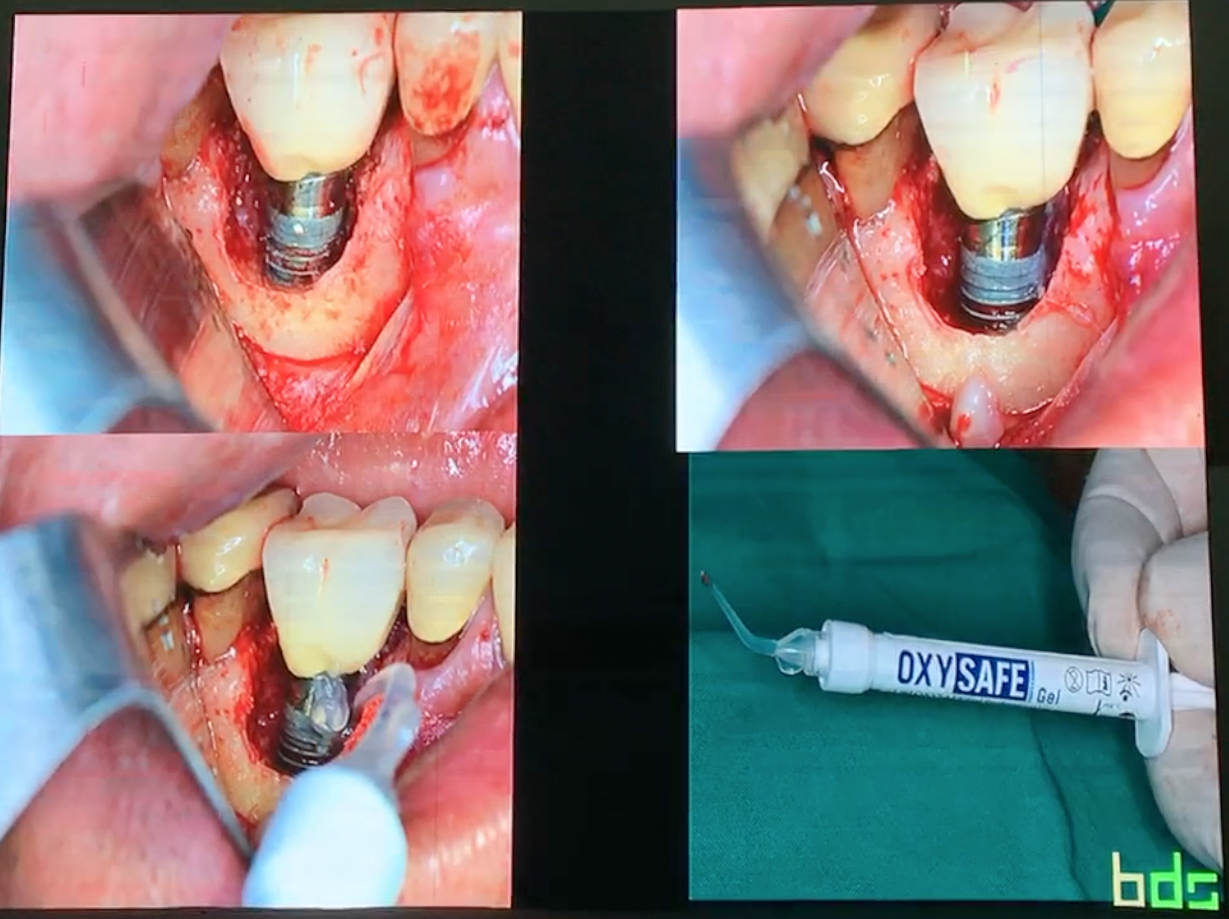

Pterygoid implants are an old therapeutic option for the

treatment of atrophic posterior maxilla that is often overlooked in today’s

treatment options. This lecture addresses the perceived anatomical risk that is

often associated with this procedure and tries to elucidate the controversies

on the subject. It will expose the scientific documentation of the procedure

and will present the modern approach in using the pterygoid implant for the

rehabilitation of totally and partially edentulous patients. The place of

guided surgery in performing this procedure is also discussed.

Length 34.30 min